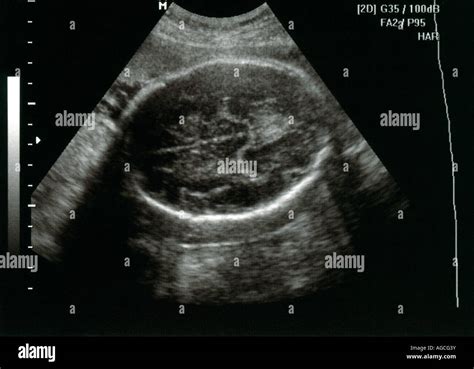

Diagnosi ecografica e protocolli di screening

La diagnosi di pielectasia avviene principalmente attraverso l'ecografia prenatale. Il protocollo attualmente in uso prevede la valutazione di neonati con segnalazione prenatale nel secondo trimestre pari o superiore a 4 mm e nel terzo trimestre pari o superiore a 7 mm. Quando la dilatazione del diametro antero-posteriore della pelvi renale supera determinati limiti, si procede a una classificazione di gravità:

- Lieve: dilatazione isolata della pelvi renale tra 7 e 10 mm nel secondo e terzo trimestre.

- Moderata: dilatazione che coinvolge anche i calici, fino a 10 mm nel secondo trimestre e fino a 15 mm nel terzo trimestre.

- Severa: dilatazione superiore a 10 mm nel secondo trimestre e superiore a 15 mm nel terzo trimestre, spesso associata ad assottigliamento della corticale renale.

È essenziale notare che la calicopielectasia è generalmente considerata di grado lieve se nel feto a termine è inferiore al centimetro. Al di sopra di questo valore, aumenta il rischio di una possibile compromissione della funzione del rene interessato.